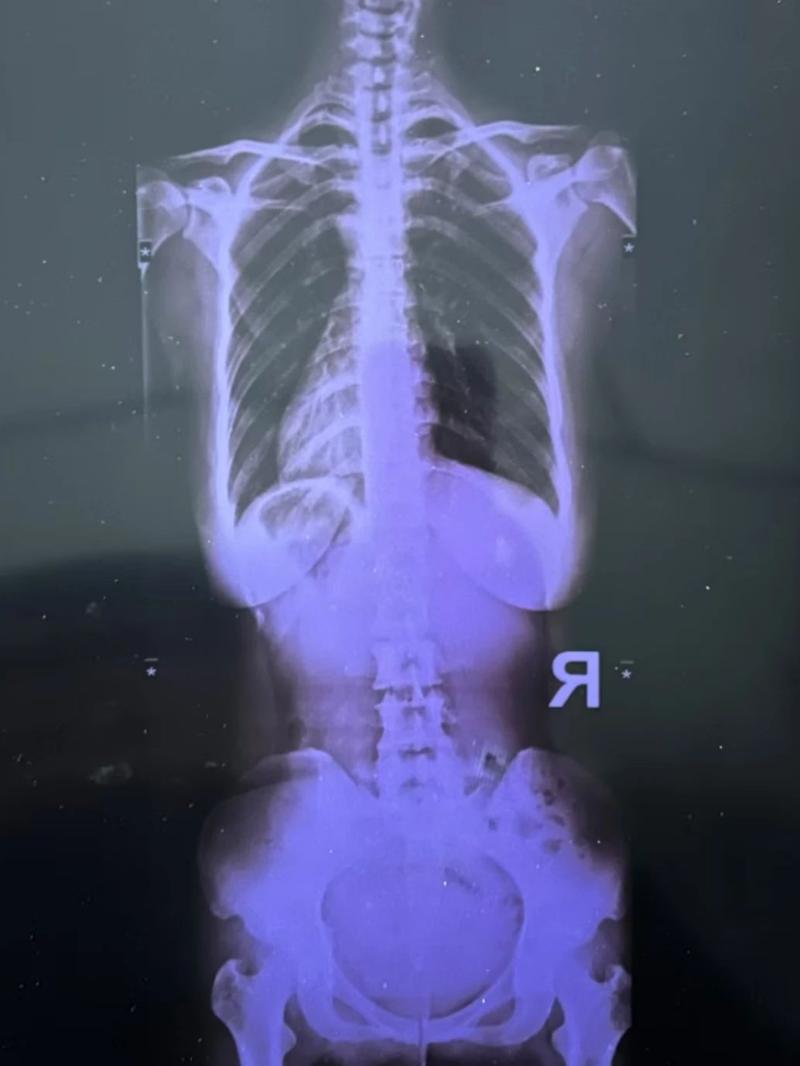

最近又疼起來嚴重影響正常生活,她前往醫院就診,結果查出了脊柱側彎11°,骨盆旋移,骶髂關節半脫位,由于這些導致頸肩,后背,腰部肌群代償出現問題,從而出現腰痛,后背痛,肩膀痛!